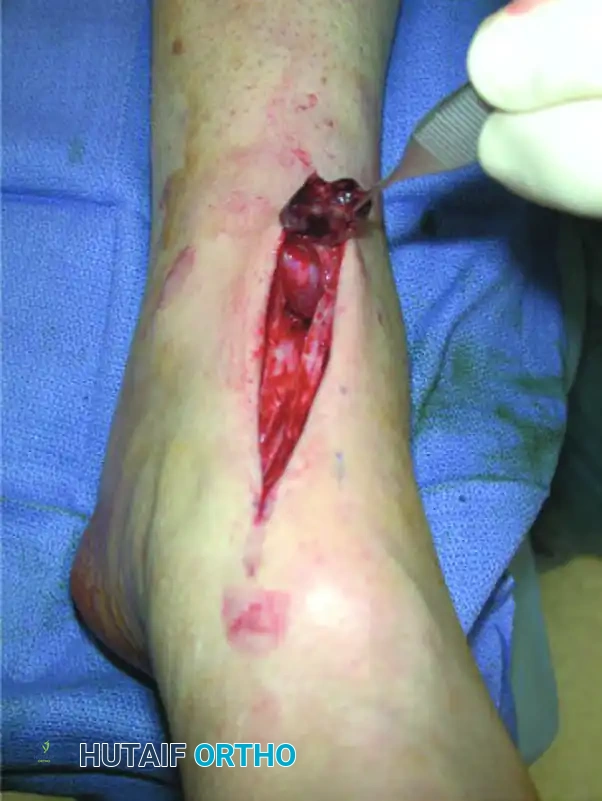

Figure 82-44: Repair of chronic anterior tibial tendon rupture. (A) Ruptured anterior tibial tendon. (B) Extensor hallucis longus tendon identified distally and anastomosed to extensor hallucis brevis before transection. (C) Extensor hallucis longus tunnel passed through a drill hole in the cuneiform. (D) Tendons fixed with suture anchors.

Figure 82-47: (A) A 61-year-old man with a rupture of the peroneus longus tendon and a varus right foot. (B) Note the hypertrophic os peroneum and its proximal migration following the rupture.